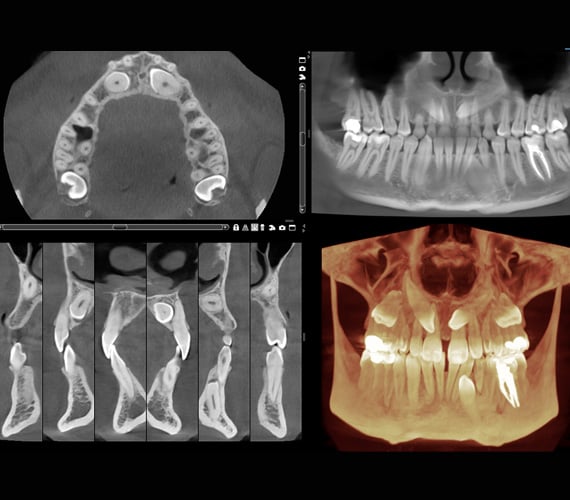

The Romexis software’s 3D rendering view provides an immediate overview of a patient’s anatomy and serves as an excellent tool for patient education. It allows you to instantly view images from different projections or converted into panoramic images and cross-sectional slices. The software’s measuring and annotation tools – such as nerve canal tracing – further support safe and accurate treatment planning.

CBCT images are ideal for orthodontic diagnoses and the Romexis software makes it easy to analyse skeletal symmetry, detect unerupted and supernumerary tooth positions, as well as identify root resorption and orientation accurately. The software can also create cephalometric images and panoramic views from CBCT images to be used for cephalometric analyses.

All our 3D imaging units have a special high-resolution mode with a 75 µm voxel size that has been specifically designed for endodontic imaging. When paired with the Romexis software’s superior visualisation capabilities, the mode is ideal for endodontic diagnostics and patient education. Root canals, traumas, root fractures and root resorption can all be easily evaluated – leading to accurate diagnoses and treatment plans.